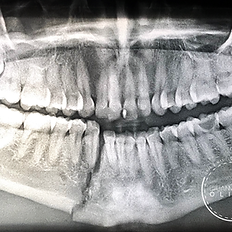

Descripción del servicio

· Las fracturas en los huesos de la cara (mandíbula, maxilar, huesos nasales, de la órbita, etc.), son el resultado de diferentes tipos de traumatismos o accidentes y repercuten a largo plazo en la función correcta así como en la estética. Un adecuado diagnóstico es la clave para el tratamiento oportuno y correcto que permita que los huesos afectados puedan recuperar su forma, función y estética adecuadamente. · Fractures in the face bones (jaw, maxilla, nasal bones, orbital bones, etc.), can be caused by different situations or accidents, they have repercussion in the function and aesthetics of the face. A correct diagnosis is the key for a successful treatment that allows the affected bones to heal properly and recover its function and aesthetics.